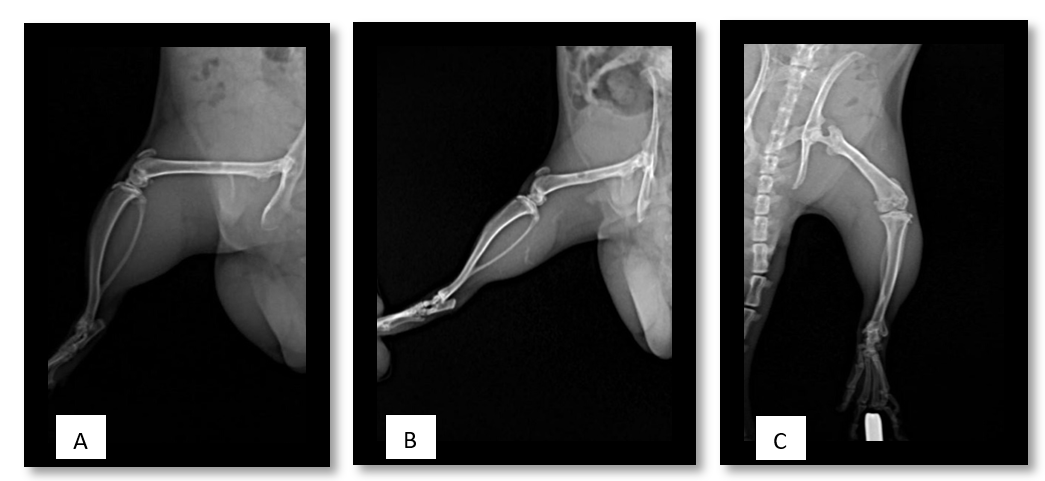

Қазіргі уақытта әртүрлі этиологиялы сүйек тінінің ақауларының стандартты емі оны ауто- немесе аллотрансплантатпен толтыру болып табылады. Алайда, пайдаланылатын аллотрансплантаттардың басым бөлігі сырттан әкелінетін болған соң көп жағдайда Қазақстан Республикасының дәрілік заттардың, медициналық мақсаттағы бұйымдар мен медициналық техниканың мемлекеттік тізілімінде тіркелмеген болып келеді. Бұл жағдай осы препараттарды Қазастанда қолдануды қиындатады. Ортопедиялық оталарға арналған шетелдік сүйек-пластикалық материалдардың жоғары құнын атап өткен тағы жөн, сонымен қатар ақауларды ауыстыру кезінде бұл препараттардың үлкен көлемі қажет болады. Остеоиндукторлық заттармен байытылған дуплексті отандық остеопластикалық материалды жасау сүйек ақаулары мен жалған буындары бар науқастарды емдеуге, мүгедектікті азайтуға, бір науқасты емдеу құнын төмендетуден экономикалық тиімділік алуға және препаратты жақын және алыс шетелдерге экспорттау мүмкіндігін береді.

Жүргізілген салыстырмалы зерттеу негізінде сүйек ақауларын толтыратын және жергілікті сүйек регенерациясын күшейтетін сүйек тінінің ақауларын емдеу әдісі әзірленеді. Бұл әдіс сүйектерді қалпына келтіру оталарының сапасын жақсартады. Бұл зерттеудің экономикалық тиімділігі - жамбас буынының эндопротездеуден кейін науқастардан алынған ортан жілік басынан аллографттарды өзіміз өндіру арқылы, аллографтты сатып алу құнын төмендету. Жоғарыда аталғандар шетелдік өндірушілерден сүйек тінін сатып алу құнын төмендетеді, Қазақстан Республикасында отандық сүйек аллографттарын өндіруге жағдай жасайды, жарақат және ортопедиялық бөлімшелерде қауіпсіз донорлық сүйекке деген қажеттілікті өтейді. Остеогенезді ынталандыру травматология мен ортопедияда емдеудің жаңа технологиясын алуға, ауруханаға жатқызу ұзақтығын қысқартуға, мүгедектікті азайтуға мүмкіндік береді, бұл экономикалық ғана емес, сонымен бірге әлеуметтік нәтиже береді.

2023 жылы сүйек ақауының жазылу динамикасын анықтау үшін гистологиялық зерттеу жүргізілді. Осы мақсатта 5 топ (әрқайсысы 30 қоян) құрылды: 1 топ – PRP бар аллографт; 2 топ – бисфосфанат қосылған аллографт; 3-топ – BMP-2 бар аллографт; 4 - BMP-2+ бисфосфонаты бар аллографт; 5-топ – аллографт қана. Оларға ортан жілігінің ақауының үлгісін қалыптастыру үшін ота жасалды. Топтардағы ақаулар әртүрлі биологиялық ыдырайтын материалдармен толтырылды. Бағалау 14 және 30 күндері жүргізілді. Гистологиялық талдау нәтижелері сүйек ақауы регенерациясының PRP және BMP-2 топтарында жаңадан пайда болған сүйек тінінің басым болуымен қарқынды жүретінін көрсетеді. BMP-2+бисфосфонат және тек бисфосфонат тобында сүйек ақауы негізінен фиброз тінімен жабылған.

- Dina Saginova, Elyarbek Tashmetov, Yevgeniy Kamyshanskiy, Marietta Arutyunyan, Ibrahim Rustambek. The histological assessment of new bone formation with zolendronic acid loaded bone allograft in rabbit femoral bone defect// Journal of medicine and life.-2023.-16(4) doi 10.25122/jml-2022-0314. (65 процентиль)

- Saginova, D.; Tashmetov, E.; Kamyshanskiy, Y.; Tuleubayev, B.; Rimashevskiy, D. Evaluation of Bone Regenerative Capacity in Rabbit Femoral Defect Using Thermally Disinfected Bone Human Femoral Head Combined with Platelet-Rich Plasma, Recombinant Human Bone Morphogenetic Protein 2, and Zoledronic Acid// Biomedicines 2023, 11, 1729. https://doi.org/10.3390/biomedicines11061729 (57 процентиль)

- Saginova, D.; Tashmetov, E.; Tuleubayev, B.; Kamyshanskiy, Y.; Davanov Sh. Effect of Platelet-rich Plasma Combined with Marburg Bone Bank-prepared Bone Graft in Rabbit Bone Defect Model// Shiraz E-Med J. 2023 September; 24(9):e136960. DOI: https://doi.org/10.5812/semj-136960 (36 процентиль)